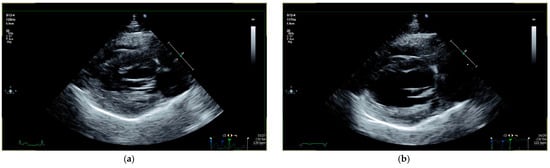

3.2. Outcome